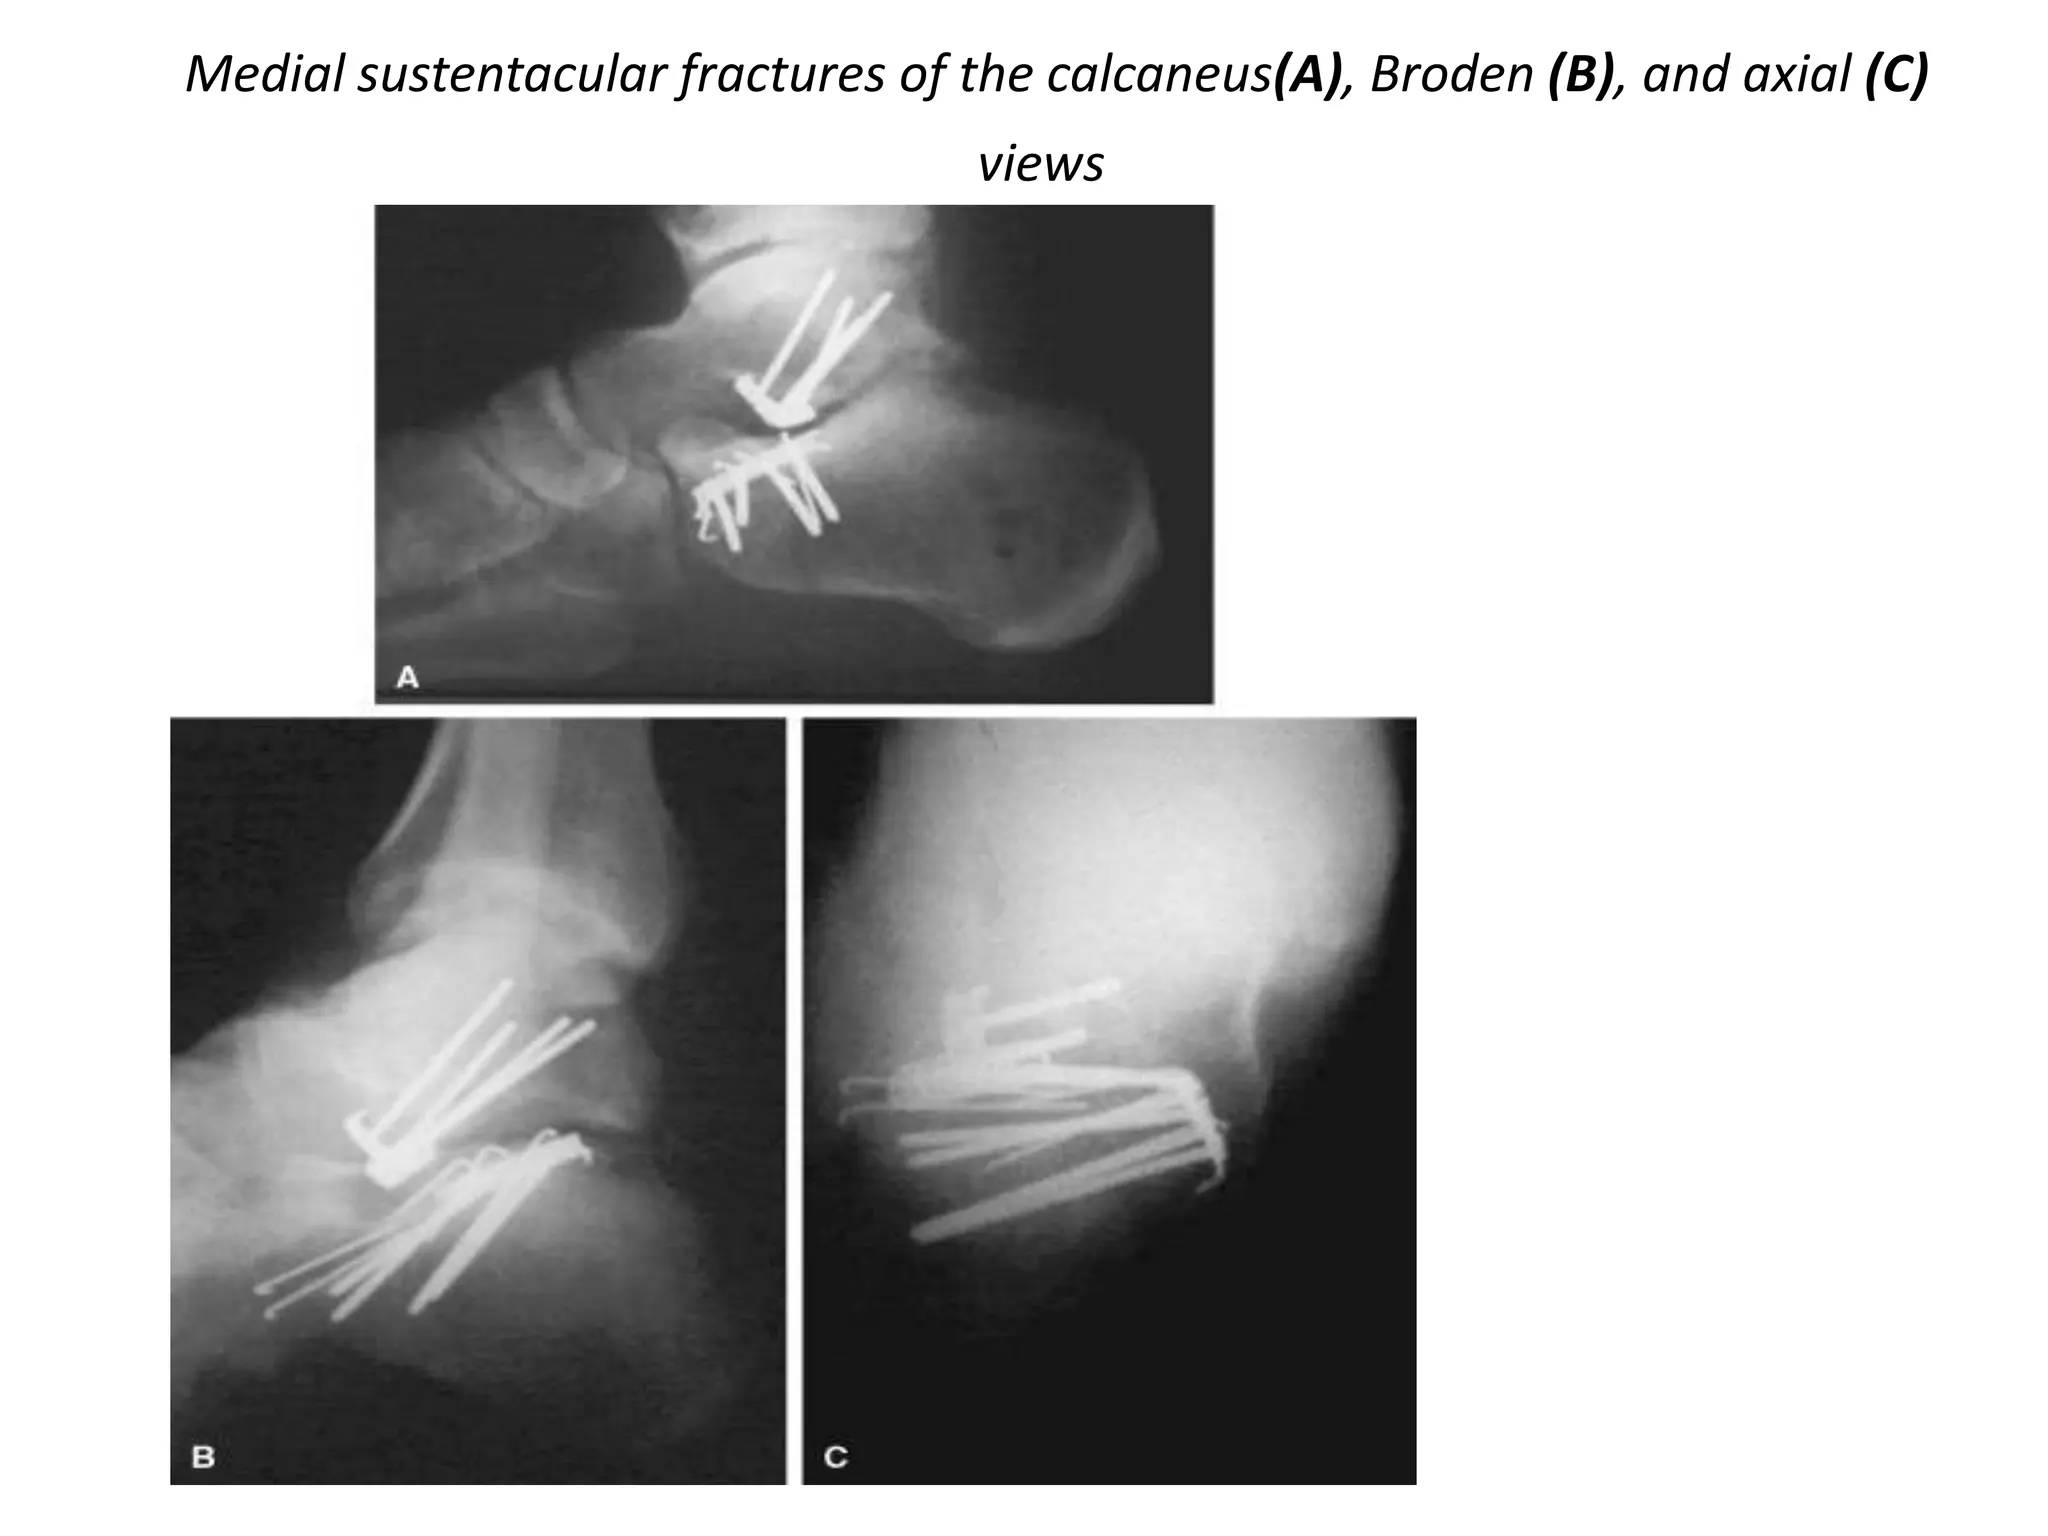

MEDIAL PROCESS FRACTURES

• Rare and usually nondisplaced

• Nondisplaced fractures can be treated with a short

leg weightbearing cast until the fracture heals at 8 to

10 weeks

• When fractures are displaced, closed manipulation

may be considered

Medial sustentacular fractures of the calcaneus(A), Broden (B), and axial (C)

views

MEDIAL PROCESS FRACTURES •Rare and usually nondisplaced • Nondisplaced fractures can be treated with a short leg weightbearing cast until the fracture heals at 8 to 10 weeks • When fractures are displaced, closed manipulation may be considered

• 117.

Medial sustentacular fracturesof the calcaneus(A), Broden (B), and axial (C) views